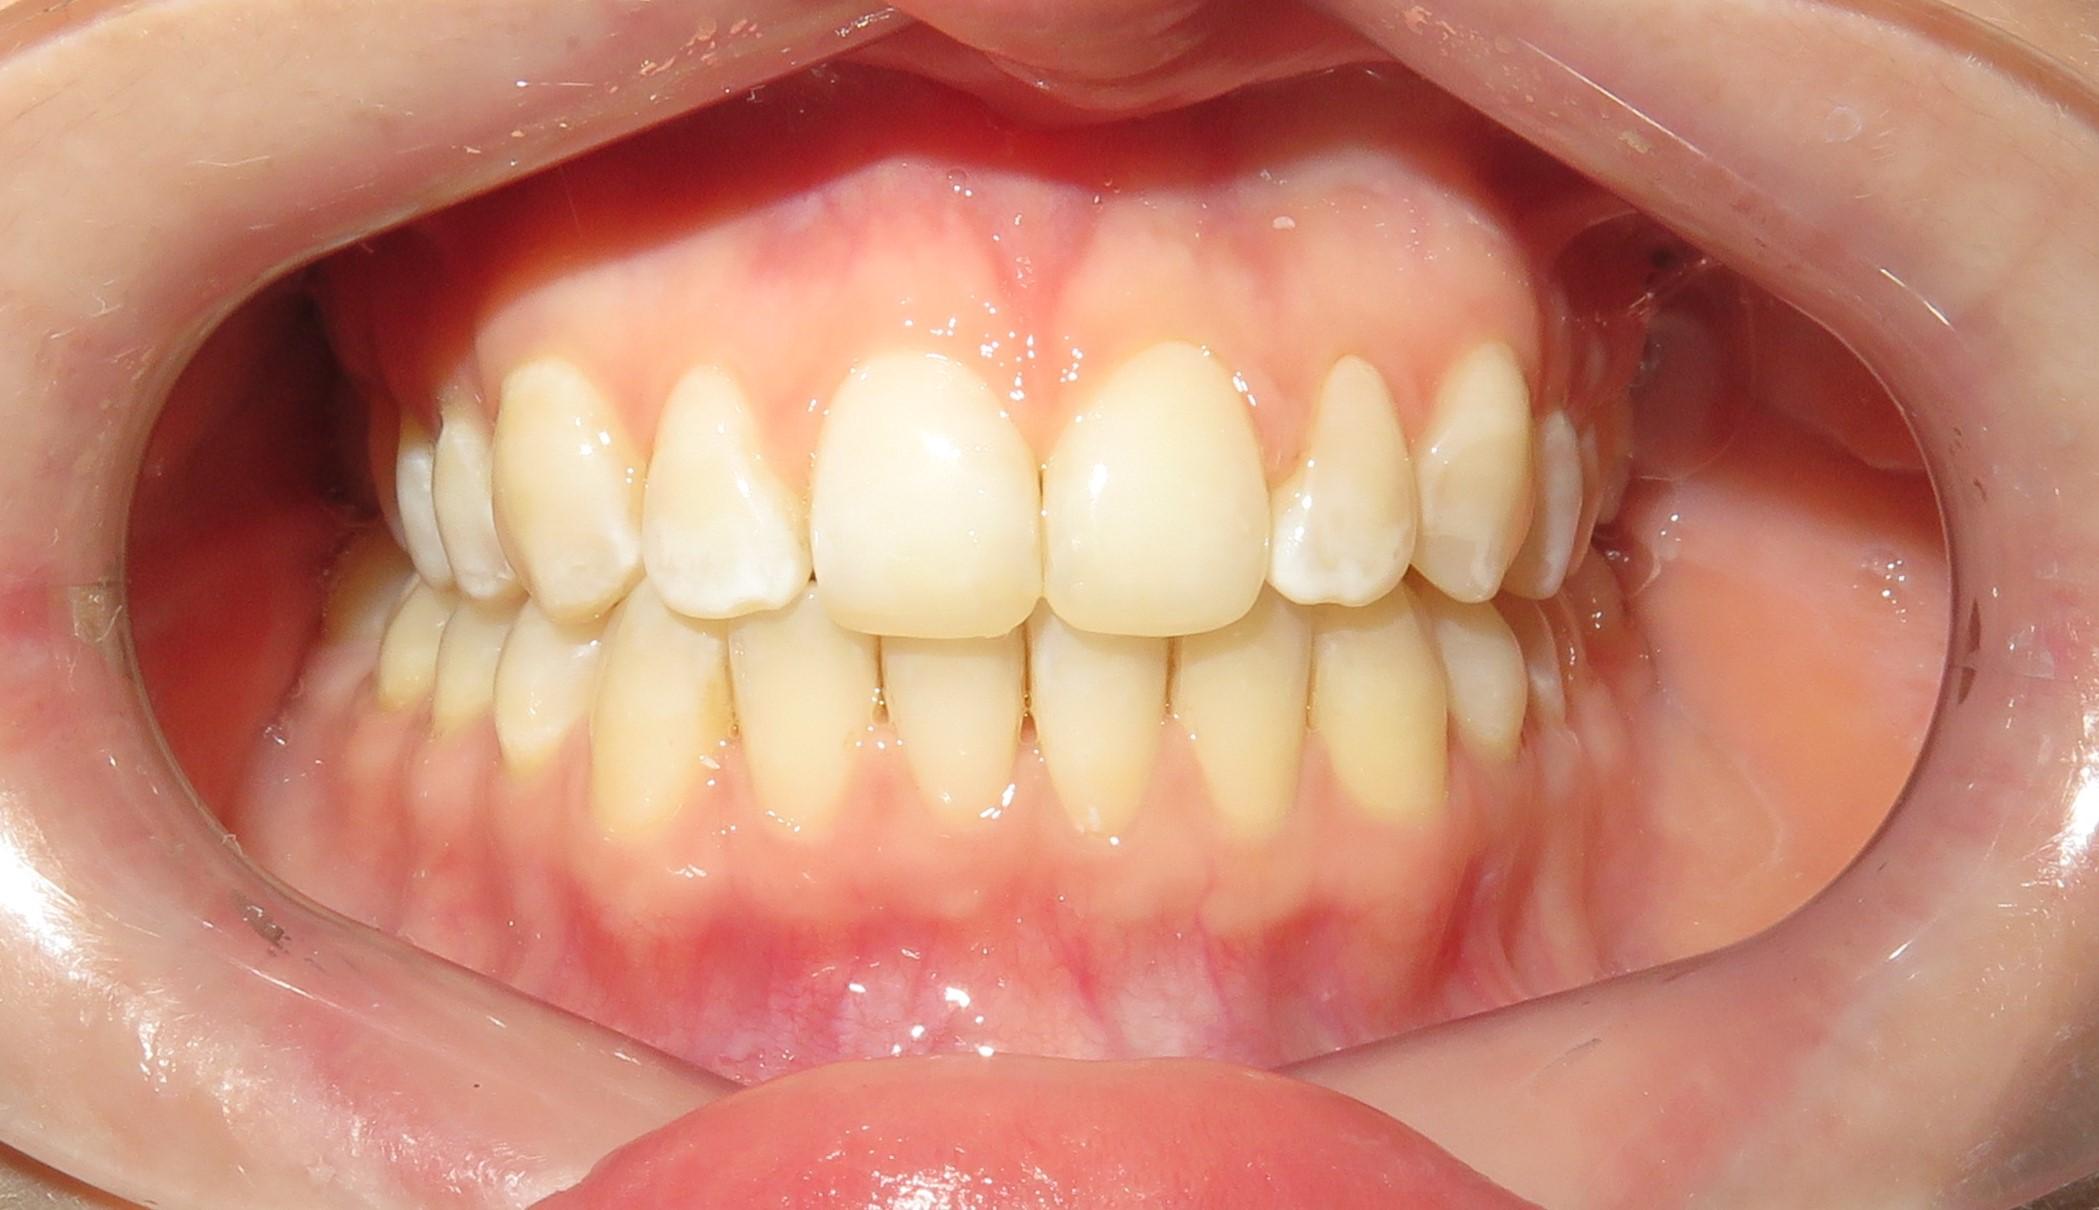

Pacjentka po kilkuletnim leczeniu ortodontycznym w innej klinice, niezadowolona z efektu końcowego, zgłosiła się na konsultacje do naszej kliniki.

Przypadek Pacjentki:

- Pacjentka nie miała zawiązków górnych dwójek.

- Wszczepiliśmy implant w miejsce górnej dwójki.

- Przeprowadziliśmy wybielanie zębów, aby uzyskać idealny odcień.

- Wykonaliśmy pełnoceramiczne licówki na górne jedynki.

- Zmieniliśmy wygląd kła przy pomocy licówki, aby wyglądał jak naturalna dwójka.

Całe leczenie trwało tylko 3 miesiące, a efekt końcowy przeszedł najśmielsze oczekiwania.

Licówki i korona na implancie wykonane przez laboratorium Dentalscan.